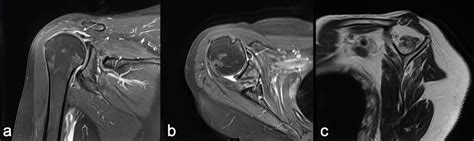

Die delaminierte Rotatorenmanschette - Orthopädie & Traumatologie ...

Versagensanalyse nach Rotatorenmanschettenrekonstruktion - Orthopädie ...